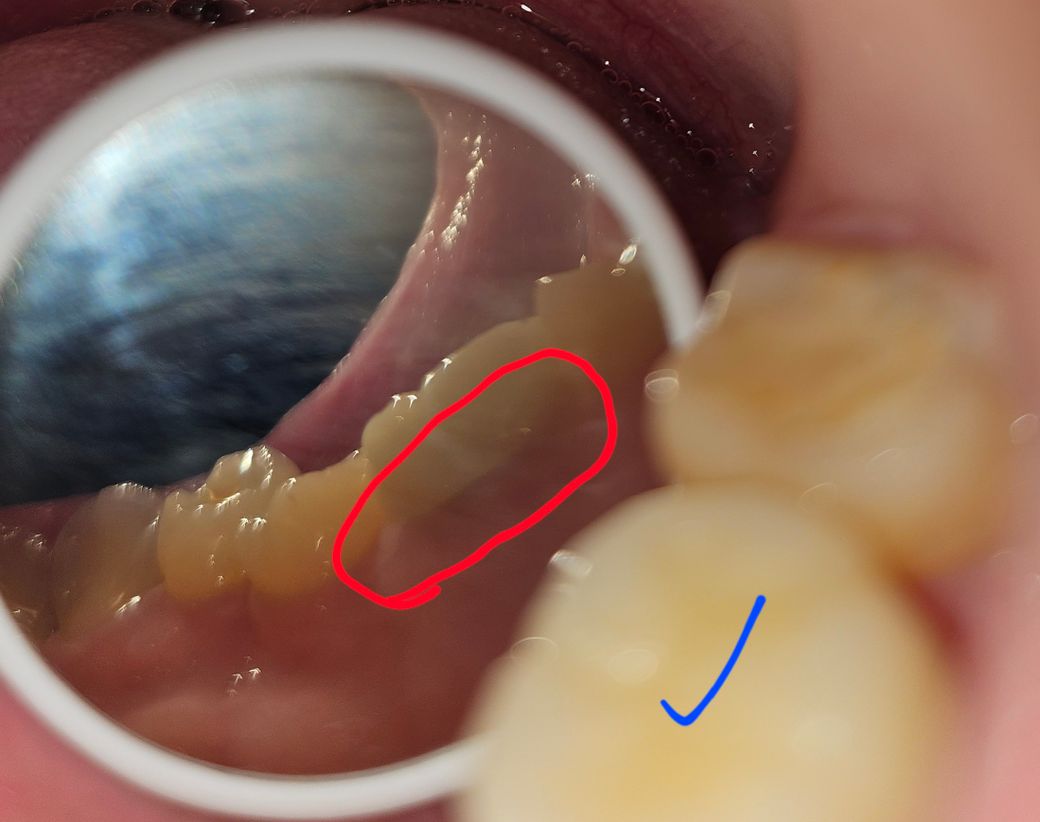

30대초반 여성입니다 작년2월쯤에 치과진료가 끝났어요 좀 큰 대공사를 했는데 그러고 통증이있다거나 그런건 아니고 지르코니아 크라운 했던곳이 이렇게 되있어서 뭔지 몰라가지고 질문을 남깁니다.. 다시 재치료는 가능한지 회색선이랑 약간 검붉어졌는데 치료끝나고 양치질 제대로 하는 방법을 보고 양치도 꼬박꼬박하고 치간칫솔이랑 치실은 절대 빼먹지 않고 하는데 충치가 생긴건지 아닌지 ㅠㅠ 혹시 임플란트를 해야하는건 아닌지 대공사할때 임플란트를 벌써 4개나 했는데 하나 더 해야하는건지 선생님들 도와주세요ㅠㅠ

파란체크가 크라운입니다

첫번째사진은 바깥쪽이구 나머지 두장은

안쪽이에요 혓바닥옆에ㅠ

• 현재 사진으로는 충치 판별이 힘듭니다. 다만 사진으로 보아서는 충치는 아닌 것으로 보여집니다. 정확한 사진의 해상도가 필요할 것으로 보이며, 크라운을 한 치아의 충치는 임상 검사를 하지 않는 이상 단순히 사진으로는 판단하기에 어려움이 있습니다.

• 지르코니아 크라운 치료를 했을 경우 치아의 내부가 검게 비춰 보일 수 있습니다. 크게 문제가 되는 것은 아니나 보철물 내부에 충치가 생겼다면 치료를 해야 할 수도 있습니다. 자세한 확인을 위해서 치과에서 진료를 받아보는 것을 권유드립니다

• 안녕하세요 치과의사 김철진입니다. 크라운은 크게 문제가 잇는건 아니고 잇몸이 내려가면서 크라운에 살짝 틈이 생긴겁니다. 관리를 잘해주시면 큰 문제는 없을꺼에요.

• 지르코니아 크라운과 잇몸 사이 경계부위에 약간 그림자가 진것으로 보입니다. 특별히 통증이 있거나 증상이 있는게 아니라면 문제가 있는 상태는 아닌 것 같습니다. 다만 해당부위 평소 치실질 꼼꼼히 해서 음식물 끼지 않도록 하면 좋겠습니다.